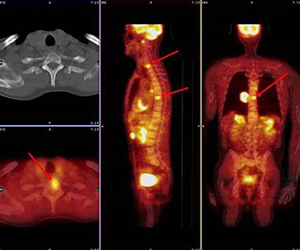

- CT or PET scan

After certain numbers of chemotherapy cycles or after certain time interval your doctor may advice to do tests like liquid biopsy or PET CT scan to see whether disease has worsened or not.